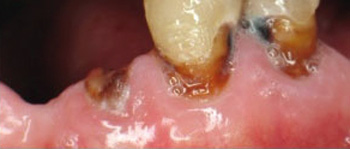

Primary demineralisation of root exposes collagen fibrils, which can lead to greater breakdown of dentine (12). Root caries lesions usually spread by covering a large surface area rather than penetrating deeply into tooth structure. Circumferential spreading of root surface caries weakens the tooth structure and increases the risk of crown fractures (Fig. 2).

Fig. 2. Progressive root caries lesions on teeth 34 and 33. Crown of tooth 32 fractured due to advanced caries.